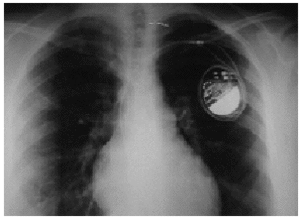

El segundo caso se presentó en una mujer de 21 años con moderado déficit intelectual a la que se le implantó un marcapasos DDDR por bloqueo auriculoventricular completo. Las radiografías y los primeros seguimientos fueron normales. Durante una revisión a los 40 días del implante, se observaron pérdida de captura del cable auricular y un ascenso del umbral en el cable ventricular. Se realizó una radiografía (fig. 3) que confirmó el Twiddler en el eje horizontal anteroposterior, con una migración total del cable auricular y migración parcial del ventricular. La enferma negaba haber manipulado el generador, pero su familia admitía que la paciente posiblemente hubiera rotado el marcapasos. Se recolocaron los cables y el generador se suturó a la fascia del pectoral.

Figura 3. Radiografía posteroanterior de tórax en la que se observa la rotación sufrida por el generador en su eje horizontal posteroanterior. El cable auricular ha perdido el contacto con el endocardio y el ventricular está a punto de desprenderse.